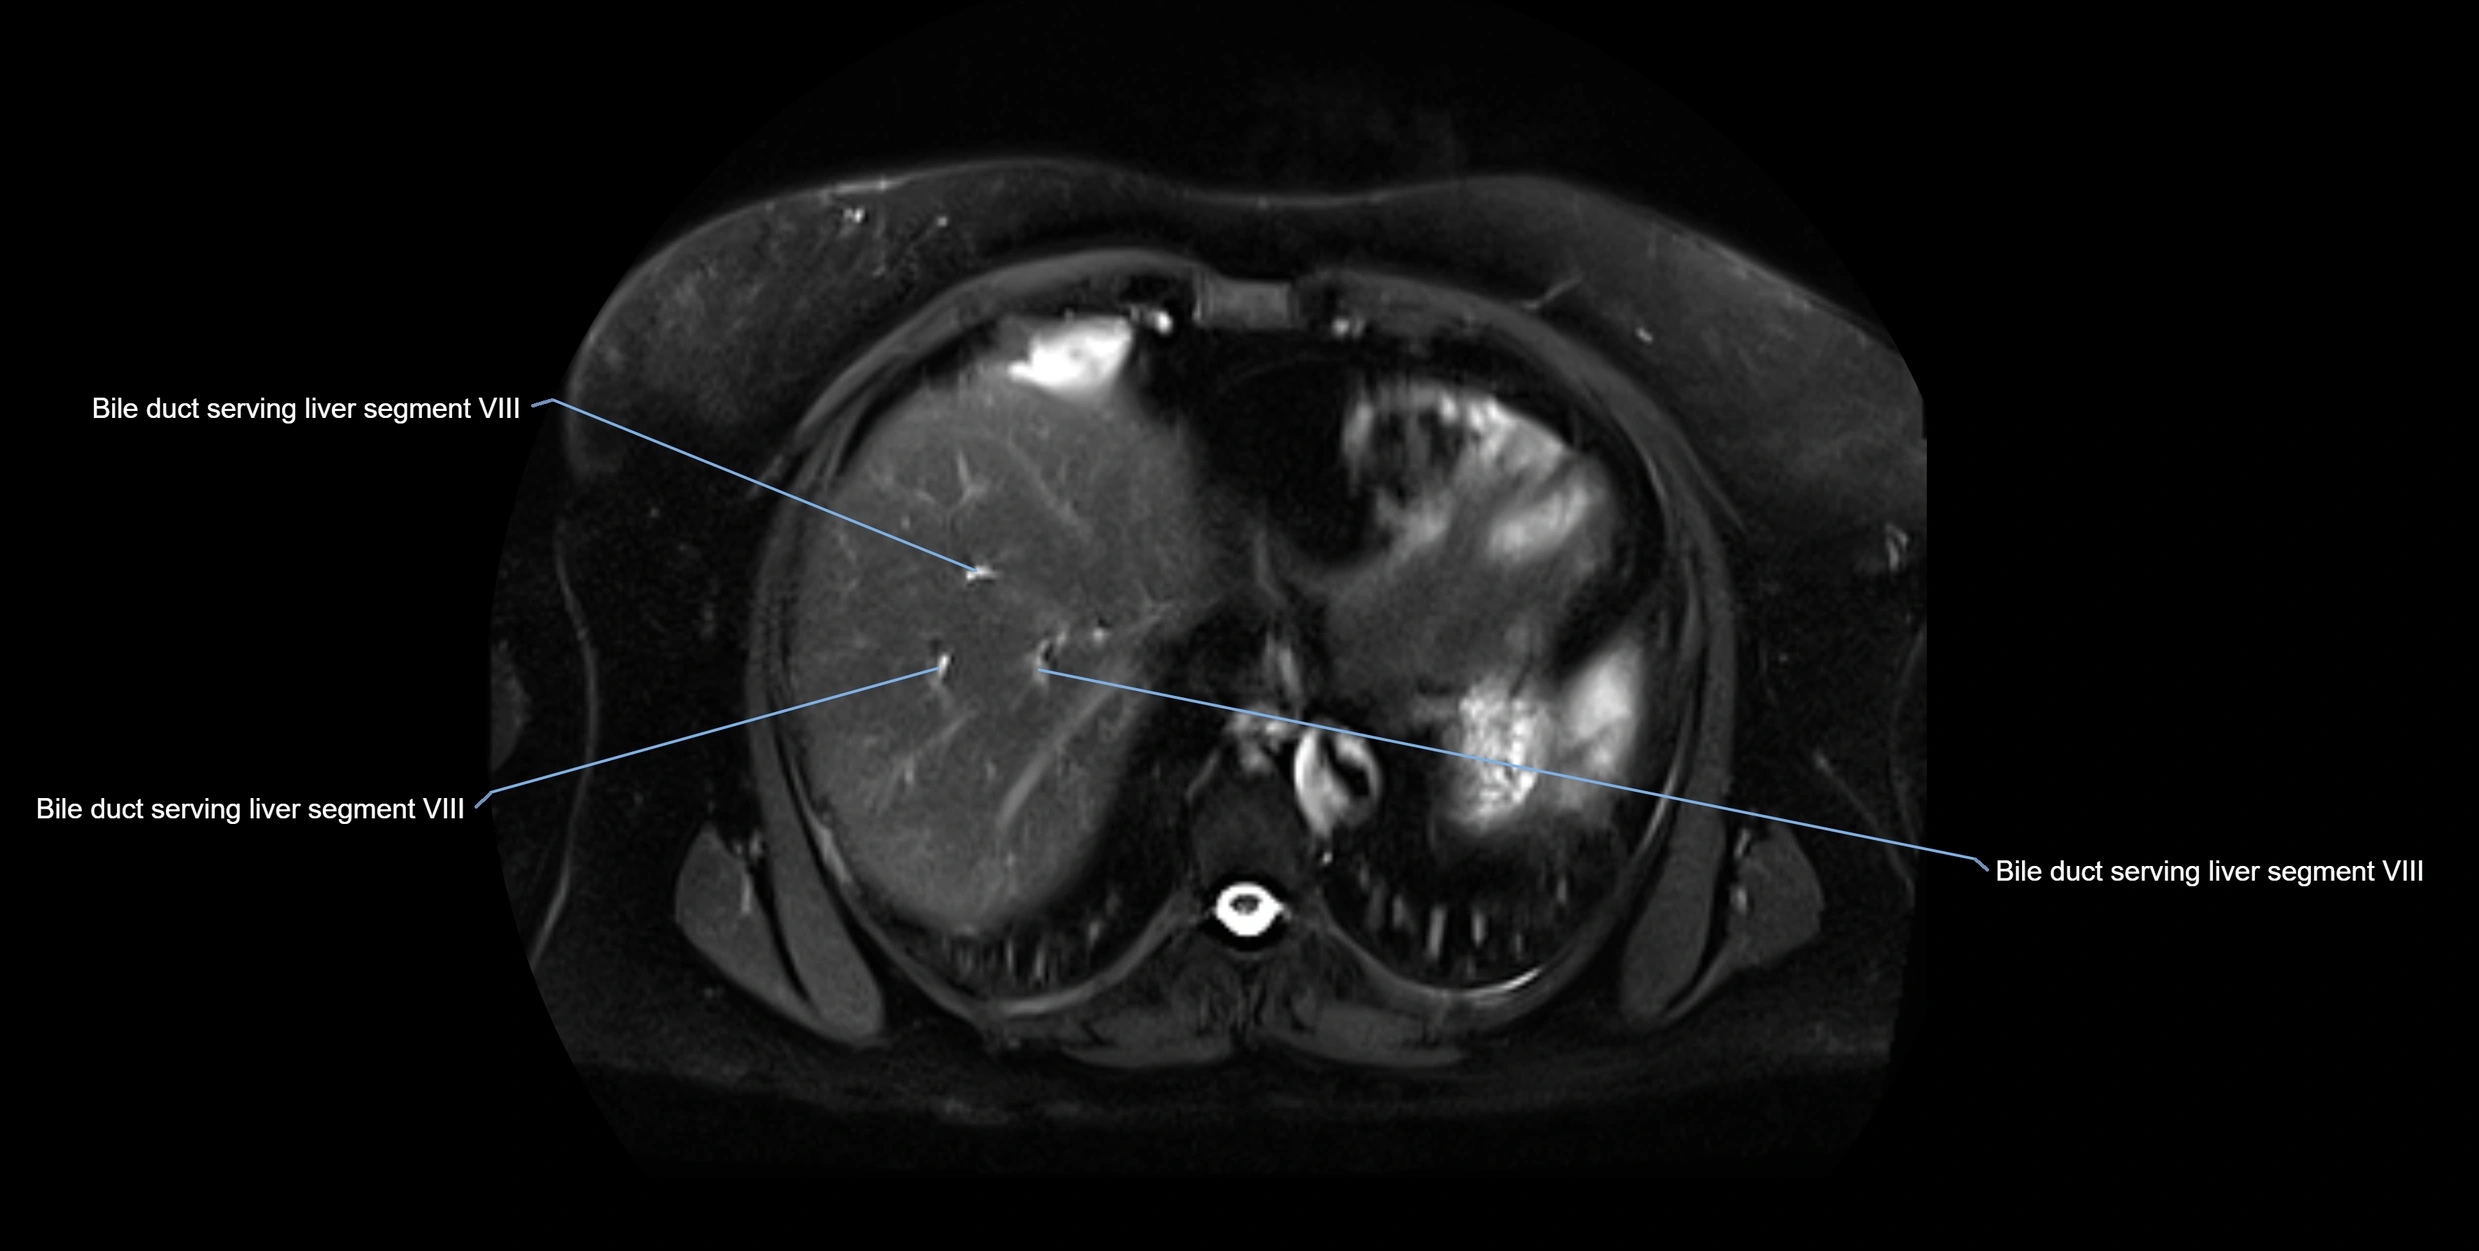

MRI image

image